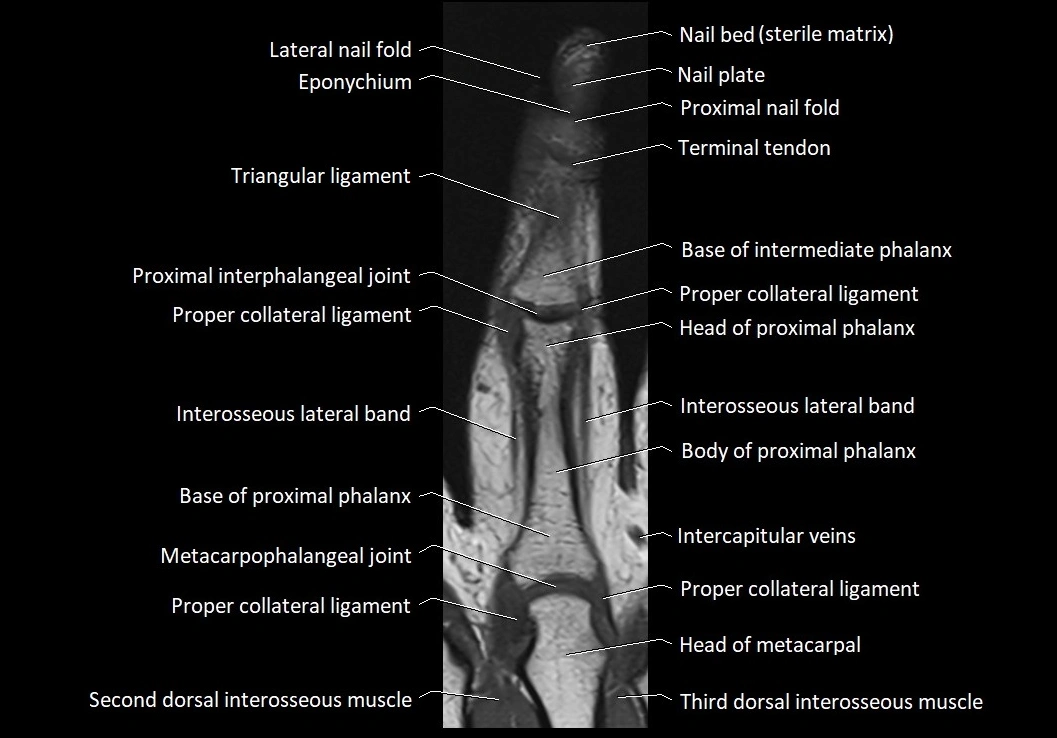

MRI images

image